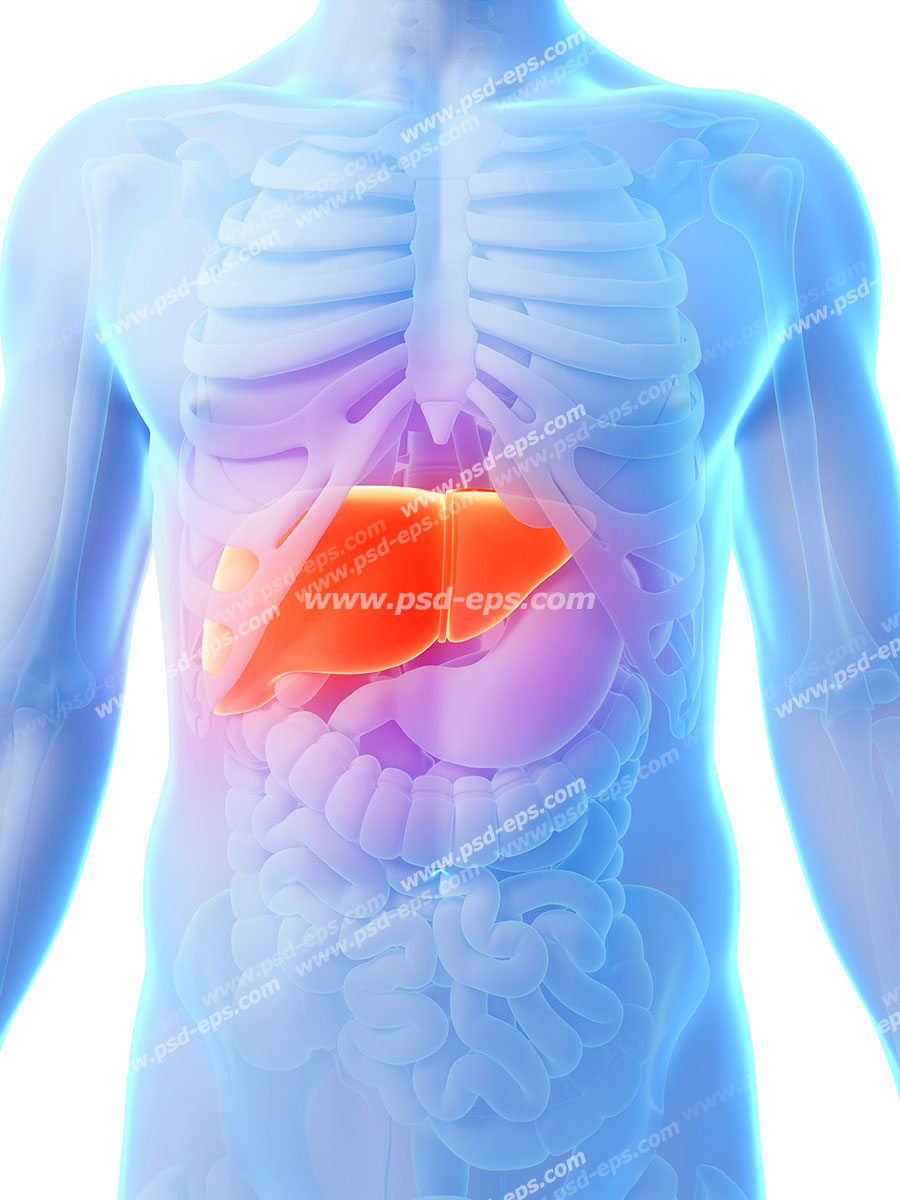

عکس داخل شکم انسان. در این همان طور که مشخص است شکم حالت بیضی شکل پیداکرده و این بیضی که کناره های شکم کشیده شده است. تعداد سلول های بدن انسان حدود ۳۷ ۲ تریلیون تخمین زده شده اند. Abdomen که در زبان عامه به غلط به آن دل نیز می گویند در آناتومی به قسمتی از تنه گفته می شود که مابین دیافراگم از بالا و سطح فوقانی لگن خاصره از پایین قرار دارد. ربات دیدنی ربات انساننمای چینی به صورت یک دختر جوان ساخته شده و جیا جیا نامگذاری شده است این ربات طوری برنامهریزی شده که میتواند صحبت کند و احساسات خود را از طریق تغییرات در چهره حالات.

شکل دوم شکم مادری را نشان می دهد که جنین دختر دارد. وحشت مادر از عکس سونوگرافی جنین داخل شکمش عکس. تصاویر جالب از داخل مغز و نخاع انسان آخرین نیوز. بدن انسان کل ساختار انسان است که سر گردن تنه سینه و شکم دو بازو و دست ها و دو ساق پا و پاها را شامل می شود.